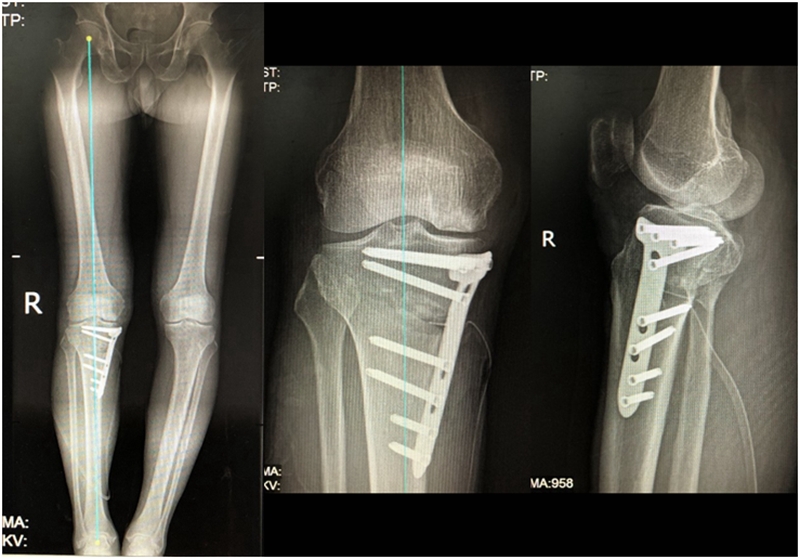

病例3:男,70岁,主诉右膝关节疼痛1年余。查体右膝无肿胀畸形,膝活动度0-120°,内侧间隙压痛。

已经累及44%的股骨内侧髁病变,半月板轻度突出,内侧后角水平撕裂

MRI上深度>20mm

治疗选择保守还是手术?

保守治疗4个月后复查

保守治疗后效果欠佳,坏死范围扩大、塌陷

翻修手术选择截骨矫形还是单髁置换?

最终选择截骨矫形

术后1年1个月

术后2年1个月拆钉

内侧半月板突出未见明显进展

病例1:男,64岁,主诉左膝关节内侧疼痛6年余。MR提示骨坏死区占比为33.28%,矢状位病变区域前后径为26.42mm,半月板相对突出百分比(RPE)31.78%,同时存在胫骨侧来源的下肢内翻畸形(MPTA83°),关节线会聚角2°。

行关节镜检查+软骨摘除+微骨折+HTO术,术后随访2年恢复良好,活动自如,行走时无左膝关节疼痛不适。